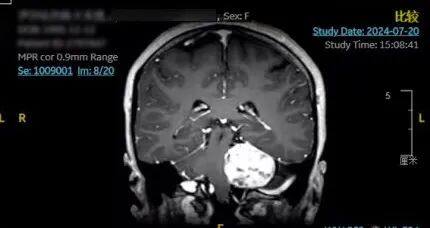

术前

来自新疆伊犁的伊孜两三年前便感觉头部时不时地会疼痛,当时的她并未引起重视。大学毕业后,伊孜来到了江苏淮安工作,近段时间逐渐发现自己的左耳听力下降、左侧鼻唇沟变浅。身体上的变化让伊孜感到十分恐慌,她连忙前往当地医院,做完头颅MRI检查后发现,导致她出现上述症状的罪魁祸首竟是长在颅内的听神经瘤!并且听神经瘤直径已经超过了4厘米,脑干受压明显。伊孜的父母得知女儿的病情后,立马从新疆伊犁来到江苏,陪同女儿到南通就诊。